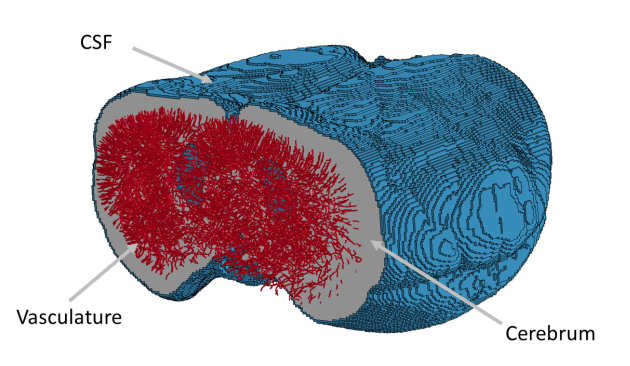

The cerebrospinal fluid (CSF) is one of the most challenging features to represent correctly in a finite element model of the head and brain. Currently, most models employ a solid element, Lagrangian mesh representation of the CSF, achieving fluid-like responses by using low shear and bulk moduli. The small space which the CSF occupies, in addition to the large relative displacement of the brain to the skull, means the Lagrangian mesh method is not well suited for this situation. This study investigates the usefulness of a particle method, Smoothed Particle Hydrodynamics (SPH), in representing the CSF in the brain. We hope to allow greater accuracy in modelling injuries which have direct relation to the relative movements of the brain, such as subdural hemorrhaging, coup and contrecoup, and chronic traumatic encephalopathy.

The cerebrospinal fluid (CSF) is one of the most challenging features to represent correctly in a finite element model of the head and brain. Currently, most models employ a solid element, Lagrangian mesh representation of the CSF, achieving fluid-like responses by using low shear and bulk moduli. The small space which the CSF occupies, in addition to the large relative displacement of the brain to the skull, means the Lagrangian mesh method is not well suited for this situation. This study investigates the usefulness of a particle method, Smoothed Particle Hydrodynamics (SPH), in representing the CSF in the brain. We hope to allow greater accuracy in modelling injuries which have direct relation to the relative movements of the brain, such as subdural hemorrhaging, coup and contrecoup, and chronic traumatic encephalopathy.